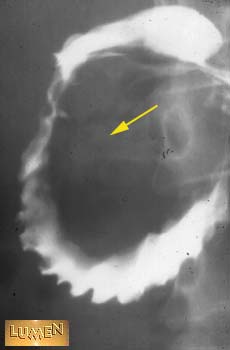

Question: What organ might cause this distortion?

Pancreas.